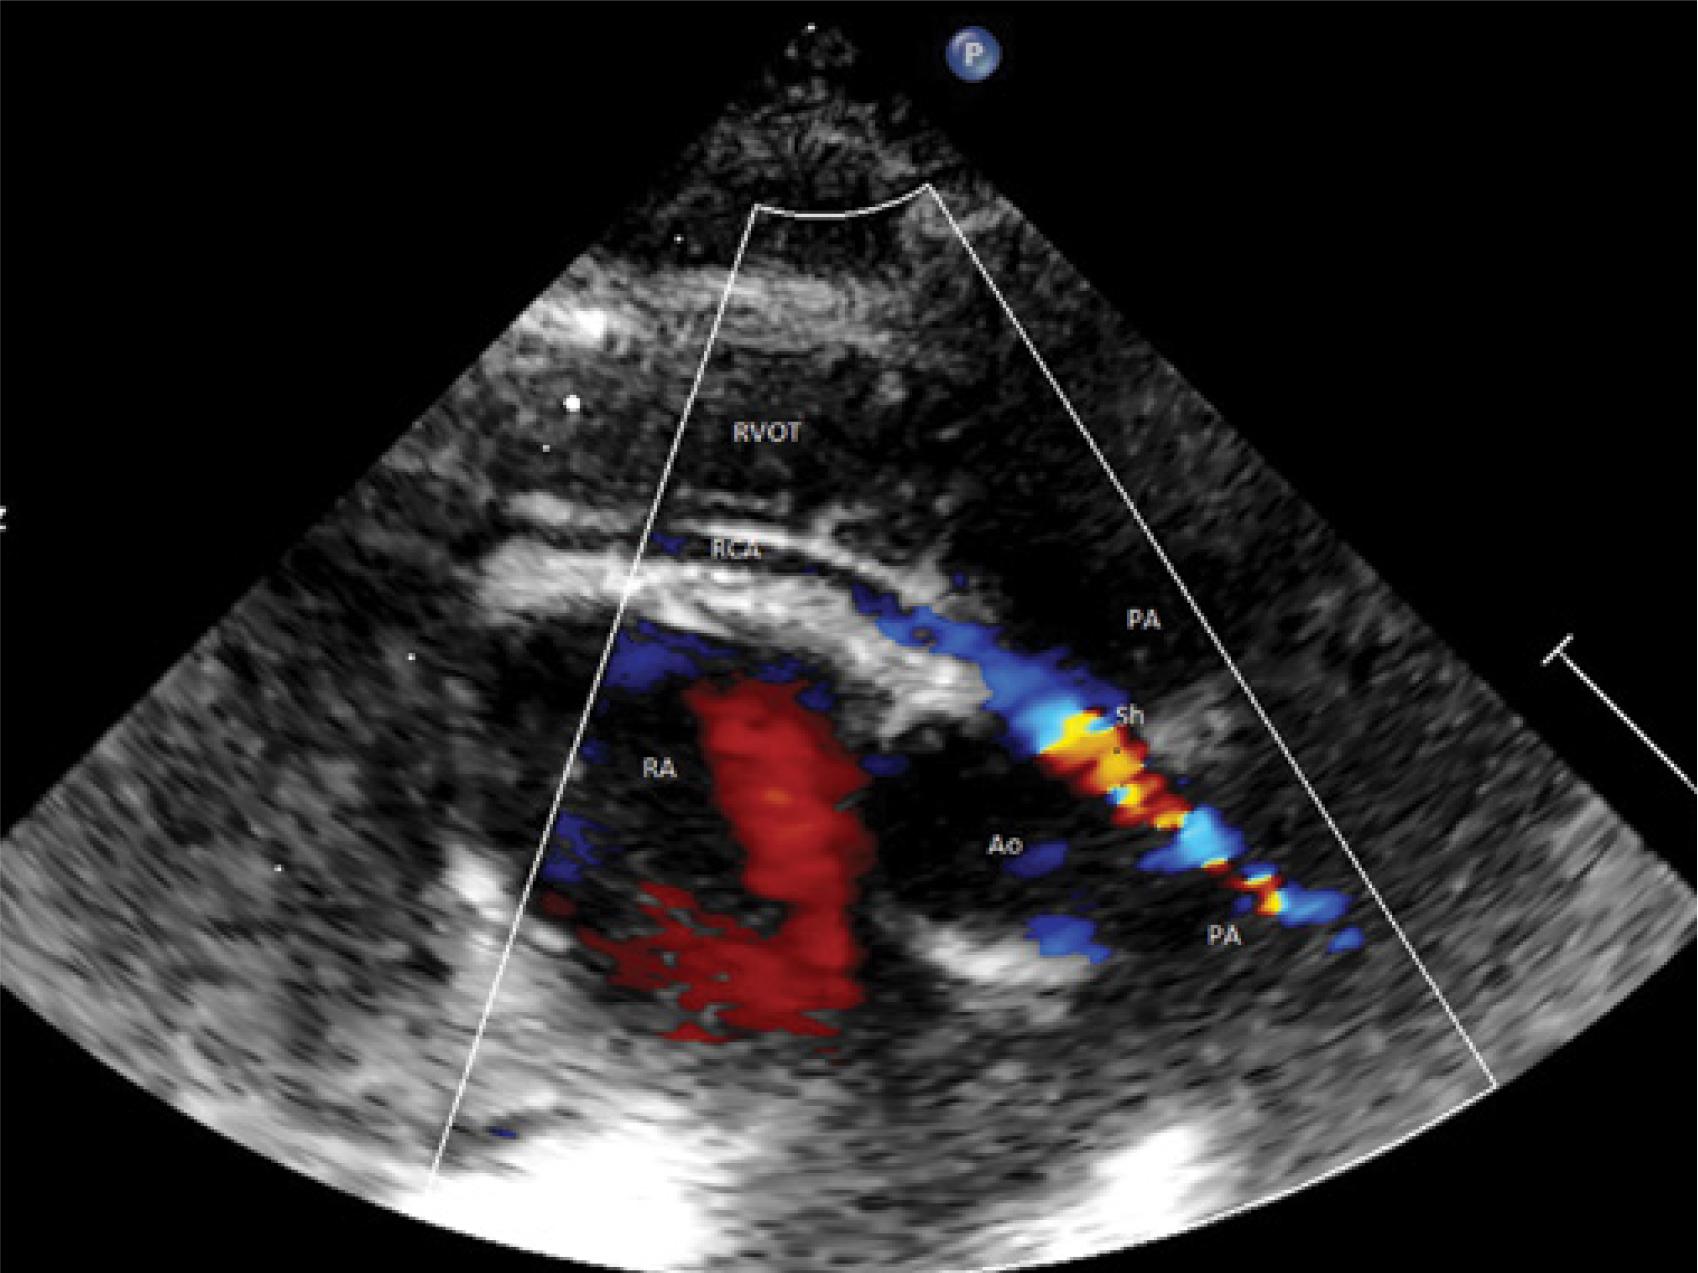

Fig. 4

Postoperative ECHO. The initial segment of the right coronary artery in postoperative examination (18 days postoperatively). In order to achieve appropriate resolving power, a linear transducer was employed along with the color Doppler scale allowing representation of low flow rates (0.15m/s). Due to the arched course of the coronary artery making it impossible to capture the entire initial segment in a single image, two image frames are presented visualizing the consecutive fragments of the vessel. Uniform, laminar flow from the aorta (red color-coded) was visualized along the entire length of the examined vessel. Ao – aortic bulb, PA – initial segment of the pulmonary trunk, RCA – right coronary artery